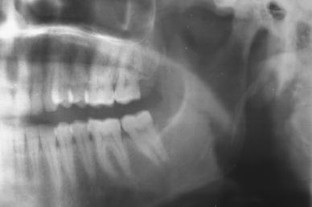

Eagle’s Syndrome: A New Surgical Technique for Styloidectomy

The purpose of this paper is to discuss the current diagnosis of Eagle’s syndrome (elongated styloid process) and to discuss a new and a much simpler technique for styloidectomy with an intraoral approach which can be used in local anesthesia. Easiness to perform, non-association of any anesthetic complications and avoidance of an extraoral scar dictates that this approach can be practiced much safely in patients with elongated styloid process.